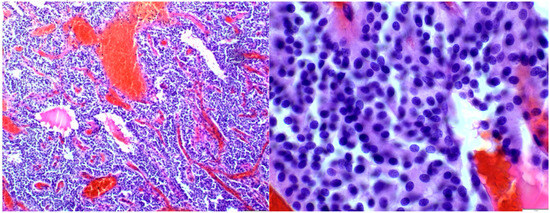

Histological examination revealed a solid and syncytial proliferation of round cells surrounding blood vessels exhibiting perivascular hyalinization. Immunohistochemical staining demonstrated positivity for smooth muscle actin (SMA) and negativity for epithelial membrane antigen (EMA), glial fibrillary acidic protein (GFAP), S100, and GATA3, consistent with a diagnosis of glomangioma (Figure 2).

Figure 2.

Histological analysis showed cohesive round cell proliferation around blood vessels with perivascular hyalinization.